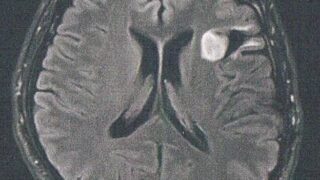

GLIOMA:手術後126ヶ月目の検査

手術から10.5年が経過した。半年ごとの定期検査です。検査概要びまん性星細胞腫グレード2(悪性転化しやすい腫瘍)MRI検査: 造影剤なし / 造影剤あり造影剤ありの場合:4時間前から絶食し、MRIの1時間前に血液検査を済ませる。診断結果MR...